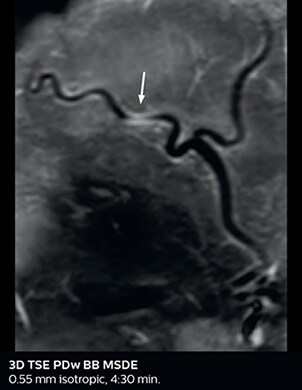

So, what is the actual impact of having more information and more diagnostic confidence? According to Dr. Savatovsky, “One of the indications I’ve seen where using Elition is most impactful is in patients with suspected giant cell arteritis. As an ophthalmologic hospital, we see many patients with suspected giant cell arteritis. Usually we were performing MRI to help us rule out an ischemic stroke, and to verify that the supra aortic vessels are undamaged. With Elition, we still do this, but now we can add on more detailed high-resolution black-blood sequences on superficial arteries. This provides us with high confidence levels for diagnosis of giant cell arteritis (GCA) and as a result, some patients are not sent for a biopsy anymore. A patient who has a normal MRI will not require a biopsy and can be discharged from the hospital in the same day. Before, such a patient would have to stay for about a week, just to find that their biopsy results were negative. We have at least three or four patients a week with suspected giant cell arteritis. For a great deal of these patients we can have a direct impact on their hospital stay.”

The 3D TSE T1w black blood MSDE sequence with fat suppression has an isotropic 0.8 mm voxel size and sagittal oblique and axial reformats are made. The images show superficial temporal artery thickening and peri-arterial fat infiltration. The 3D TSE PDw black blood MSDE with fat suppression has 0.55 mm isotropic voxels. The images shows focal involvement of the frontal branch of the superficial temporal artery.